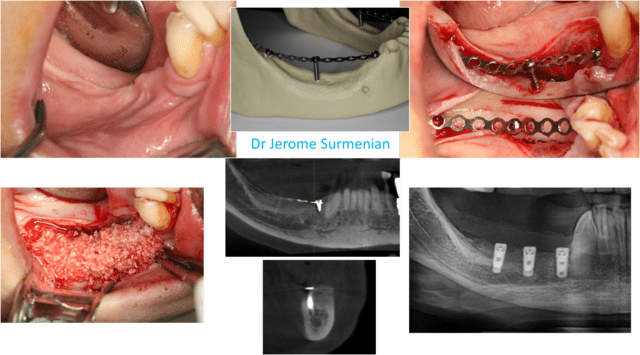

Quant au Fast system, voici qq images qui vous permettront de constater comment un protocole basé sur un concept biologique peut vous permettre de réaliser une augmentation osseuse verticale ou horizontale de manière simplifiée. Pour plus de détails, rendez-vous à la formation organisée à Sallanches le 6 décembre (chez Euroteknika) avec 2 chirurgies en direct..

un autre cas mandibulaire "hot": Fast system et A-PRF..

La résorption s'arrête toujours à la tête des vis ou de la mesh..